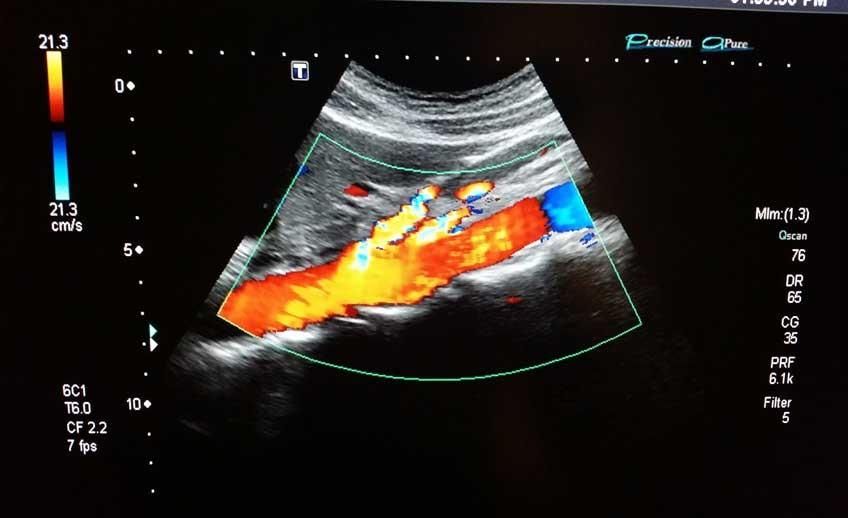

🔹 سونوگرافی داپلر (Doppler Ultrasound): برای بررسی جریان خون در رگها، عروق و شریانها.

🔸 سونوگرافی داپلر: برای بررسی جریان خون در بند ناف و قلب جنین.